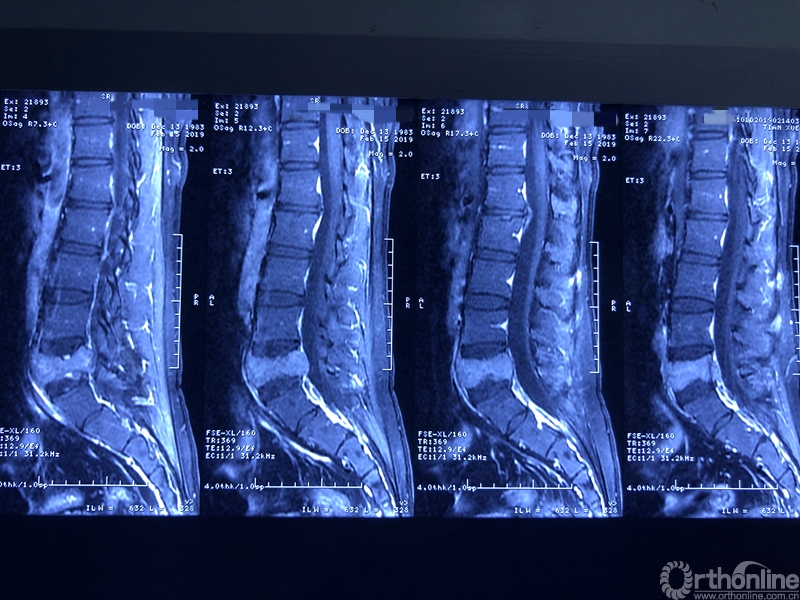

据介绍,患者为39岁男性,在一年前开始出现腰部反复疼痛的症状,休息下后疼痛还可以缓解,当时并未引起患者重视。过年后感觉疼痛加重,赴当地医院检查。核磁共振显示腰椎上长了一个鹅蛋大小的肿瘤,不偏不倚地侵蚀在第五节腰椎上,正是腰椎和骨盆连接部位附近。于是患者来同济医院骨科就诊。

就诊前CT

通过对患者详细的身体检查、穿刺活检和综合评估后,确诊患者是腰椎骨巨细胞瘤,第五腰椎破坏70%以上,邻近软组织也有破坏。这种肿瘤属于交界性的有恶性倾向的良性肿瘤,若不彻底切除,患者疼痛会逐渐加剧,甚至因骨质坍塌而瘫痪,若肿瘤细胞转移更会危及生命。若是能在早期尽快彻底、完全地切除肿瘤及被侵蚀椎体,病人才很可能完全战胜肿瘤。